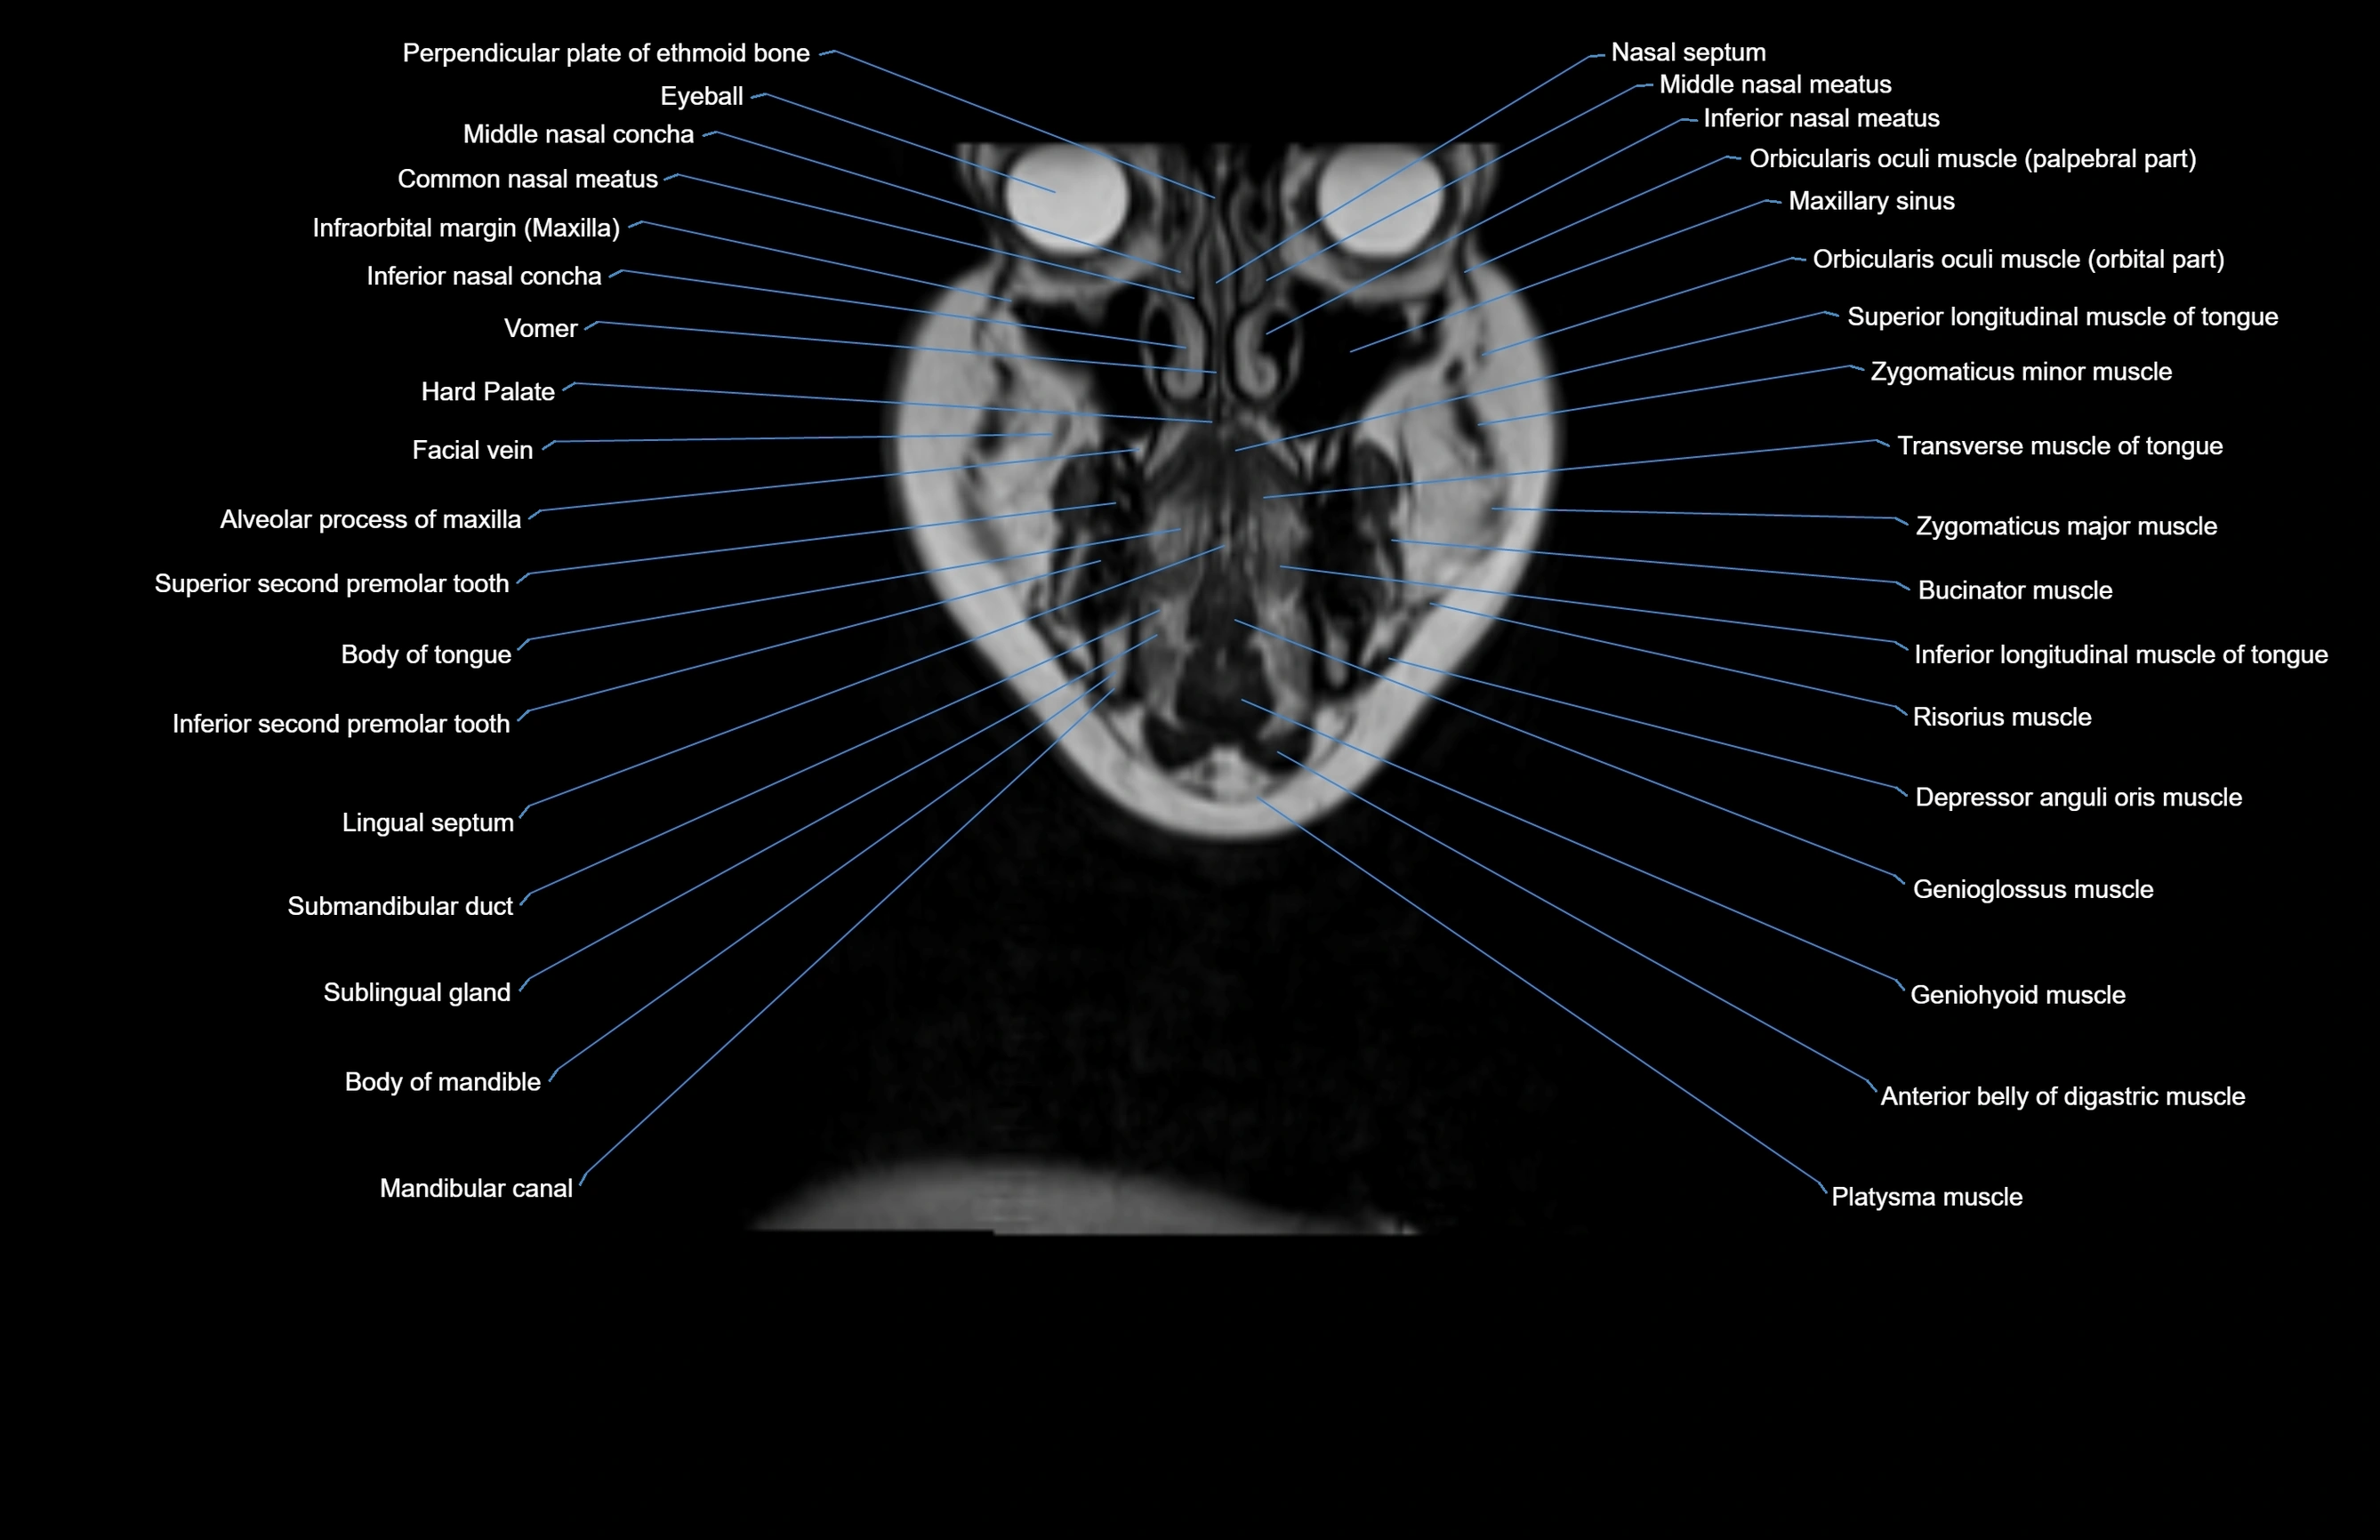

- Alveolar process of maxilla

- Body of tongue

- Common nasal meatus

- Hard palate

- Inferior longitudinal muscle of tongue

- Inferior nasal meatus

- Mandibular canal

- Middle nasal concha

- Nasolacrimal duct (Tear duct)

- Orbicularis oculi muscle

- Orbital part of orbicularis oculi muscle

- Sublingual gland

- Submandibular duct

- Submandibular gland